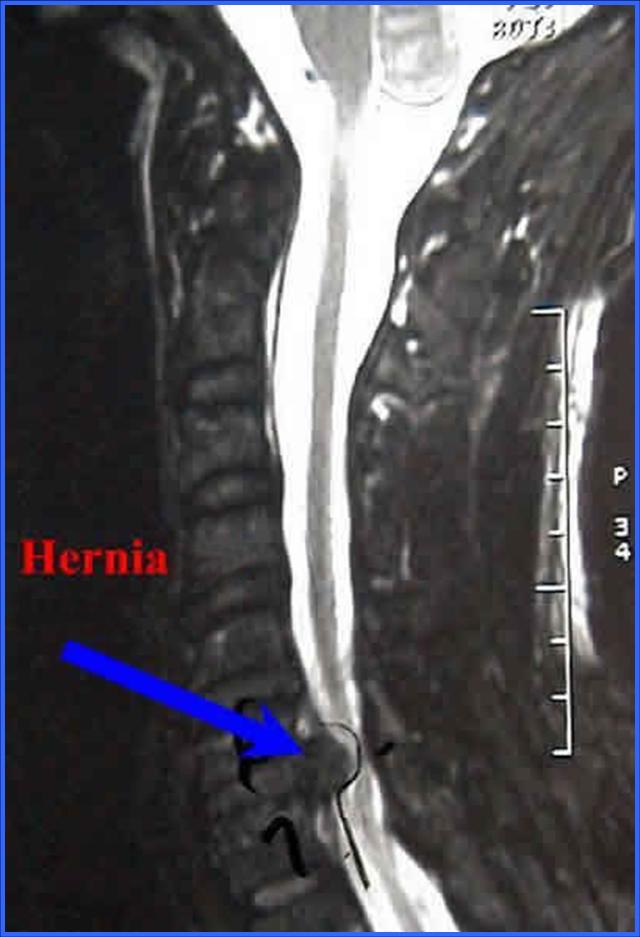

HERNIAS DISCALES DE LA COLUMNA CERVICAL

Los discos cervicales pueden herniarse al igual que los lumbares, con lo que se comprime la raíz nerviosa provocando dolor en la extremidad superior alteraciones de la sensibilidad o de las fuerzas, sensación de frío o calor y hormigueos. El diagnósticos se hace mediante el examen Clínico y la Resonancia Magnética.